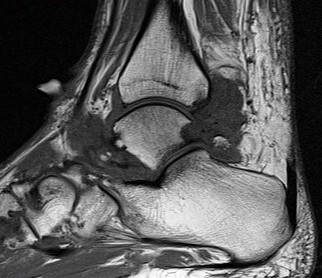

Figure 3 for case Gout arthritis ( RID3567 )

Figure 3